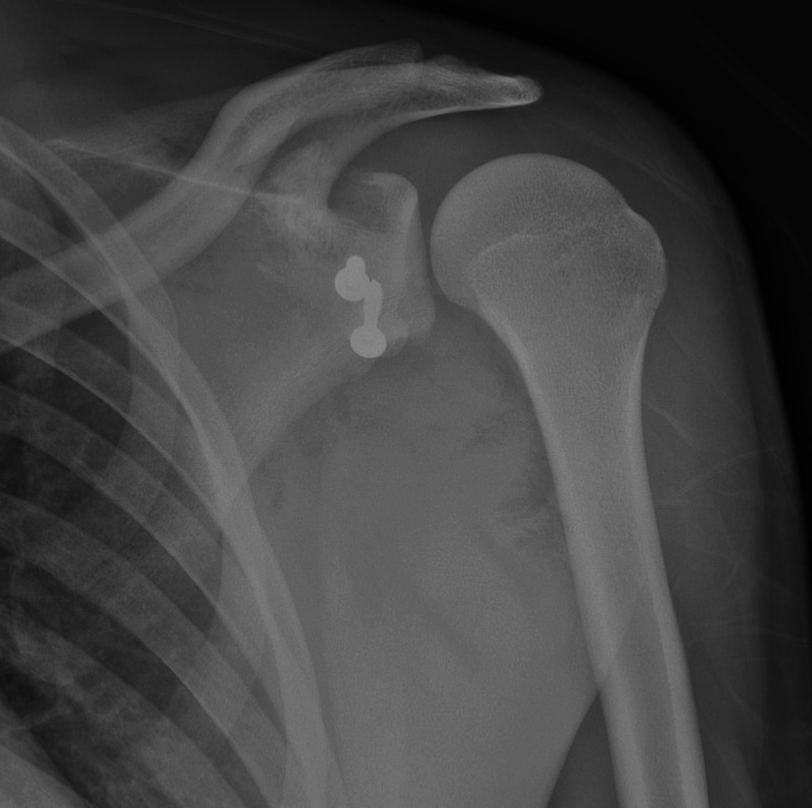

The operation involves transferring a small piece of bone, along with its attached tendon, from the coracoid process to the front of the glenoid.

This bone graft increases the size of the socket, while the tendon provides a dynamic sling effect that stabilises the shoulder during movement. Together, these mechanisms significantly reduce the risk of future dislocations.